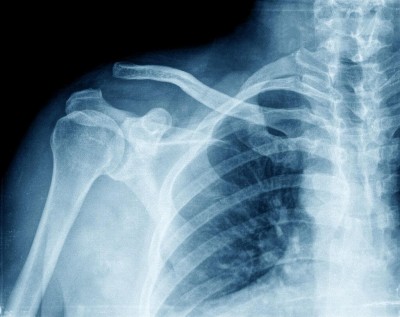

Na reclamação trabalhista, o empregado disse que fora admitido, por concurso público, para a função de carteiro e, após concurso interno, passou a carteiro motorizado. Em razão de fortes dores no ombro direito, realizou exames em que foi constatada lesão do manguito rotador, grupo de músculos e tendões da articulação do ombro, causada pelo levantamento de cargas.

O relator do recurso de revista do carteiro, ministro Alberto Bresciani, votou pela majoração do pensionamento vitalício para 100% do seu salário. Ele observou que o artigo 950 do Código Civil assegura às vítimas pensão que corresponda à importância do trabalho para o qual ficou inabilitado, na proporção da incapacidade, além das despesas com o tratamento e os lucros cessantes. No caso analisado, o TRT concluiu que o empregado, em razão das doenças apresentadas, está total e permanentemente incapacitado para a função de carteiro motorizado.